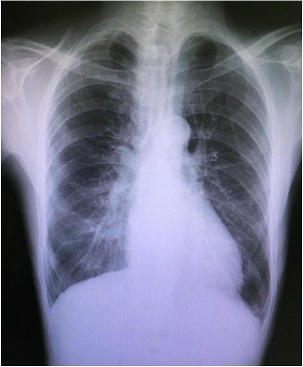

Preoperative Blood Pressure (BP) and Heart Rate (HR) at rest were 145/88 mmHg and 98 beats/min, respectively. In addition, preoperative blood test showed the following abnormalities: Hemoglobin (Hb):10.1 g/dL, Hematocrit (Hct):9.8%, Blood Urea Nitrogen (BUN):45.7 mg/dL, and Creatinine (Cr):10.18 mg/dL. Moreover, electrocardiography indicated left ventricular hypertrophy. He didn’t have myocardium ischemia on the myocardial perfusion scintigraphy, and the pulmonary congestion was not detected in his chest X-ray (Figure 1). Transthoracic echocardiography revealed a left ventricular ejection fraction of 60%. Wall motion disorder and heart failure were not confirmed, but the patient was diagnosed with severe AS and grade III MR (Figure 2) (Table 1). Although he did not have syncope history, he had exertional dyspnea. New York Heart Association functional classification was class II and American Society of Anesthesiologists physical status was class III, respectively. In this case, because his cardiac function was kept, we decided to prioritize the oral surgery to prevent postoperative endocarditis of aortic and mitral valve replacement [6].

Figure 2: Echocardiography pictures of the aortic valve (light) and the mitral valve (left).